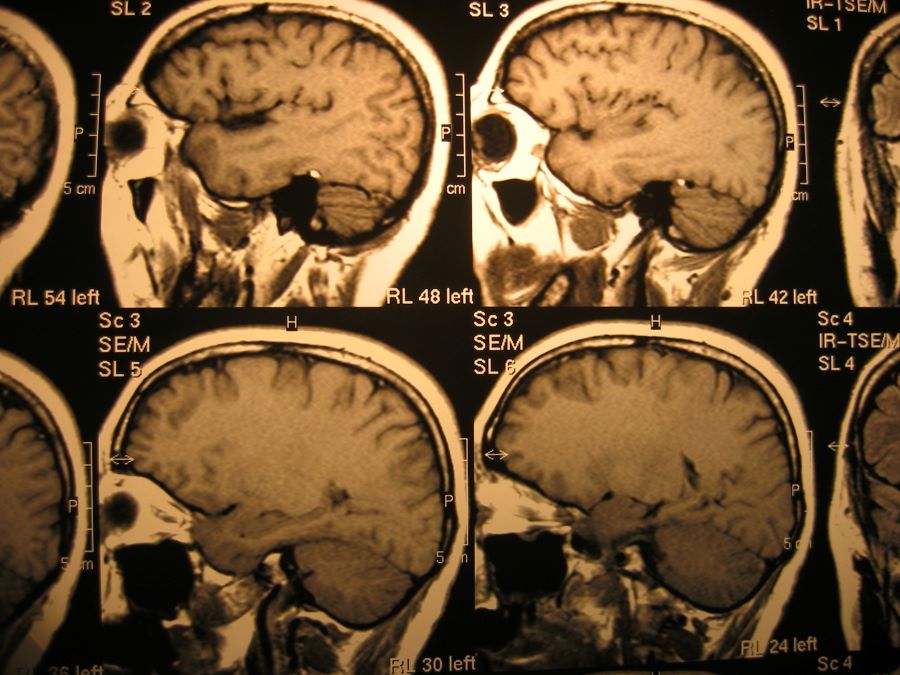

‘Elektroconvulsietherapie levert geen hersenschade op’

13-12-2023 Uit recent onderzoek van UMC Utrecht blijkt dat elektroconvulsietherapie (ECT), dat wordt toegepast bij ernstige depressie, het hersenweefsel in de hippocampus niet beschadigt. Het lijkt er ook op dat de therapie het vermogen van de hersenen om zichzelf te reorganiseren bevordert. De studie vergroot…